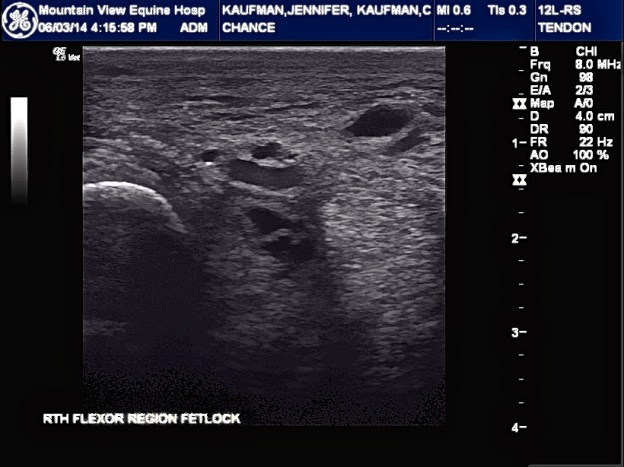

The vet arrived, gave him a shot of Banamine and an antihistamine and confirmed that Chance had a fever of 102 degrees and had Lymphingitis. There was no visible abrasion, puncture, or lump… I asked the vet to do x-rays to ensure that he did not have a break in his leg. The x-rays confirmed that there was no break. The vet suggested a regiment of antibiotics, steroids (I really am against using steroids due to the short-term and long-term side effects but in this case, I would try anything to make sure he was comfortable) , prevacox, and a antacid to protect Chance from stomach related issues from the medications. It was also advised to continue to cold hose or ice and keep his legs wrapped and Chance stall bound.